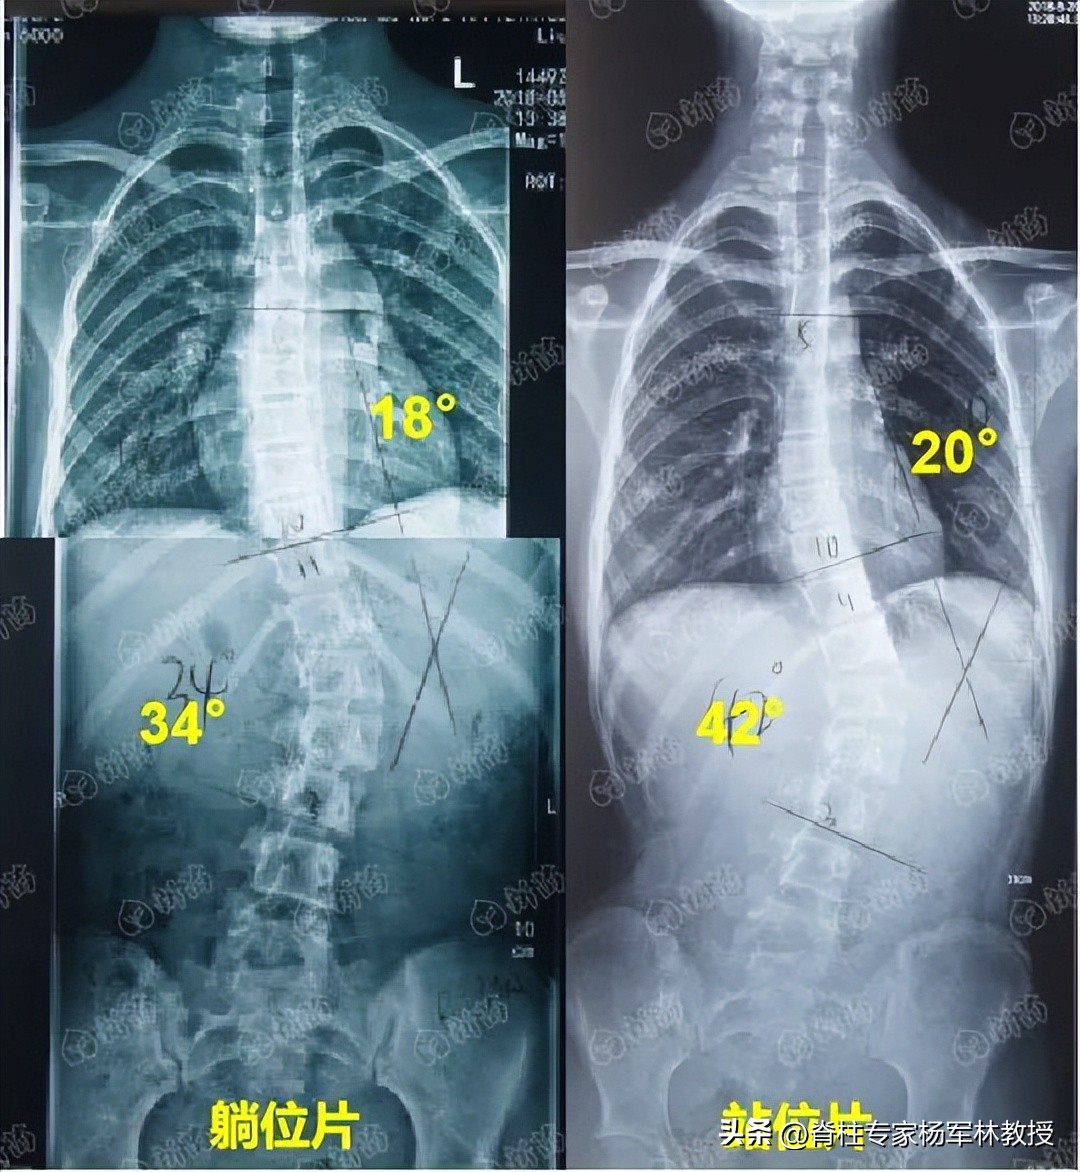

下图是一位患者站着拍和躺着拍的全脊柱X光片,度数竟然相差了8°!

图片源自:新苗团队

大多数时候,我们都是站着或坐着,脊柱保持站立位的状态,所以站着拍摄全脊柱X光片最接近日常状态,能够准确的判断脊柱真实情况。

而躺着的时候,脊柱不受重力和压力作用,处于最放松的状态,拍摄出的片子则会比实际侧弯较轻,这会影响病情评估和治疗方案的选择。